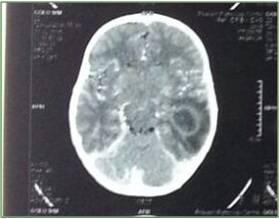

A nine year old, male child presented in the emergency with 2-3 episodes of seizure, high grade fever and respiratory distress since 15 days. Seizure were of generalized tonic clonic type and was associated with drooling of saliva, uprolling of eyeball, spontaneous micturition of urine and cyanosed limb and face. Immediately intravenous lorazepam 2mg were given in bolus dose and intubated with PVC cuffed endotracheal tube 6 mm ID and controlled mode of ventilation were started. This was accomplished by rapid sequence intubation technique using inj thiopentone 5mg/kg and inj rocuronium 1mg/kg. Then patient was shifted to intensive care unit, where bedside 2D-echocardiography and chest roentogram were done. The 2-D echocardiography revealed atrioventricular and ventriculo atrial concordance, D-TGA, large patent foramen ovale, right to left shunt, moderate pulmonary artery hypertension and the chest roentogram revealed egg on side appearance with presence of infiltrates in the Right Lower Lobe. Routine investigations, blood culture, tracheal tube culture and serum procalcitonin levels were sent. Antibiotic coverage were started in view of suspected aspiration during seizure and a non-contrast CT scan of brain were ordered following seizure episode which revealed ring enhancing lesion in left temporal lobe causing mild mass effect and moderate surrounding edema with abnormal leptomeningeal enhancement (S/O: Abscess? Tubercular?). Laboratory investigations showed Hb-22.4g% with Hct-64.9%, platelets counts- 142,000/mm3, and Total leucocyte count-14,600/mm3 with normal liver and renal function tests

Incidence of preoperative morbidity and mortality.7,8 Suggested modalities for the treatment of this occurrence are hyperventilation with an inspired oxygen concentration (FiO2) of 1.0, judicious administration of volume, use of vasoconstrictors to elevate SVR, and control of wide variations of the heart rate.6–8 Hence judicious preoperative hydration is very necessary. Till date there is no conclusive anaesthetic plan for TGA with brain abscess. Preoperatively, an understanding of the patient’s underlying pathophysiology, coupled with knowledge of the effects of anesthesia on the anomalous myocardium, is crucial. Although extensive preoperative evaluations by the patient’s intensivist, cardiologist, and cardiac surgeon are preferable, they may not be readily available, as were the case with this patient. Careful review of the patient’s preoperative medication profile, with attention to potential anesthetic interactions, must be considered (Figure 1 & 2).

Figure 2